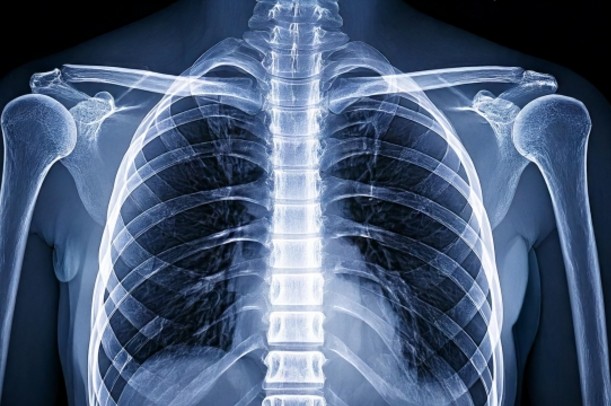

肋間神経は、胸椎(背骨の胸の部分)から出て、肋骨の下を弓状に走っています。

この神経が刺激されると、痛みは肋骨の走行に沿って背中からわき腹、胸前部まで伝わることがあります。

「チクッ」とする局所的な痛みだけでなく、帯のように広がる「放散痛(ほうさんつう)」が出るのも特徴のひとつです(引用元:済生会「肋間神経痛とは」)。

特に、片側だけに痛みが集中するケースが多く、左右同時に出ることはまれとされています(引用元:AJ Clinic「肋間神経痛の症状と原因」)。